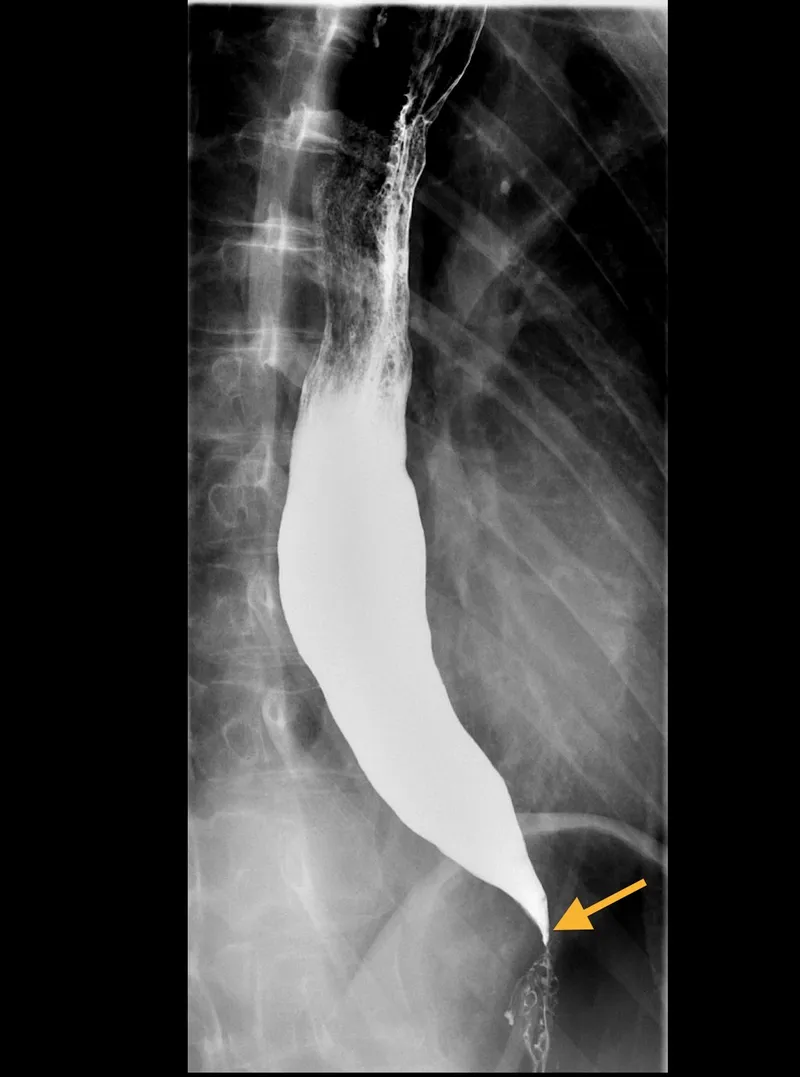

Barium Swallow: Initial for structural lesions (strictures, webs, rings). Useful for achalasia ("bird beak" appearance).

- Achalasia Cardia:

- LES non-relaxation, esophageal aperistalsis.

- 📌 Bird's Beak on barium swallow. Dysphagia (solids & liquids).

- Achalasia: "Bird-beak" on barium, impaired LES relaxation.